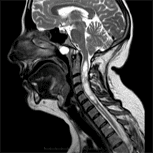

我們是一家位於西班牙巴塞隆納的國際專科醫療中心,不設分院,專注於精準且高品質的醫療照護。我們採用微創手術從病因治療Arnold-Chiari I型症候群、特發性脊髓空洞症與脊柱側彎等相關疾病,致力於為來自世界各地的患者帶來更安全、更有效的治療選擇。

你有Chiari畸形第一型、 脊髓空洞症或是脊柱側彎嗎?